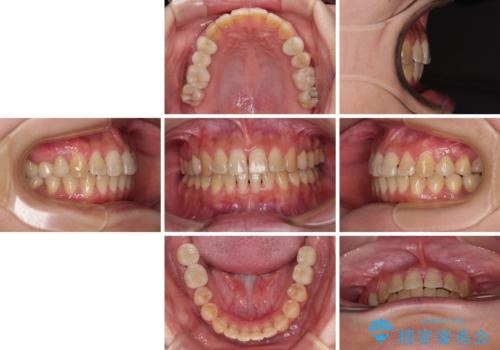

治療の期間と費用はかかりますが、初診時とは比べものにならないほど良好な状態にて治療を終えることができました。